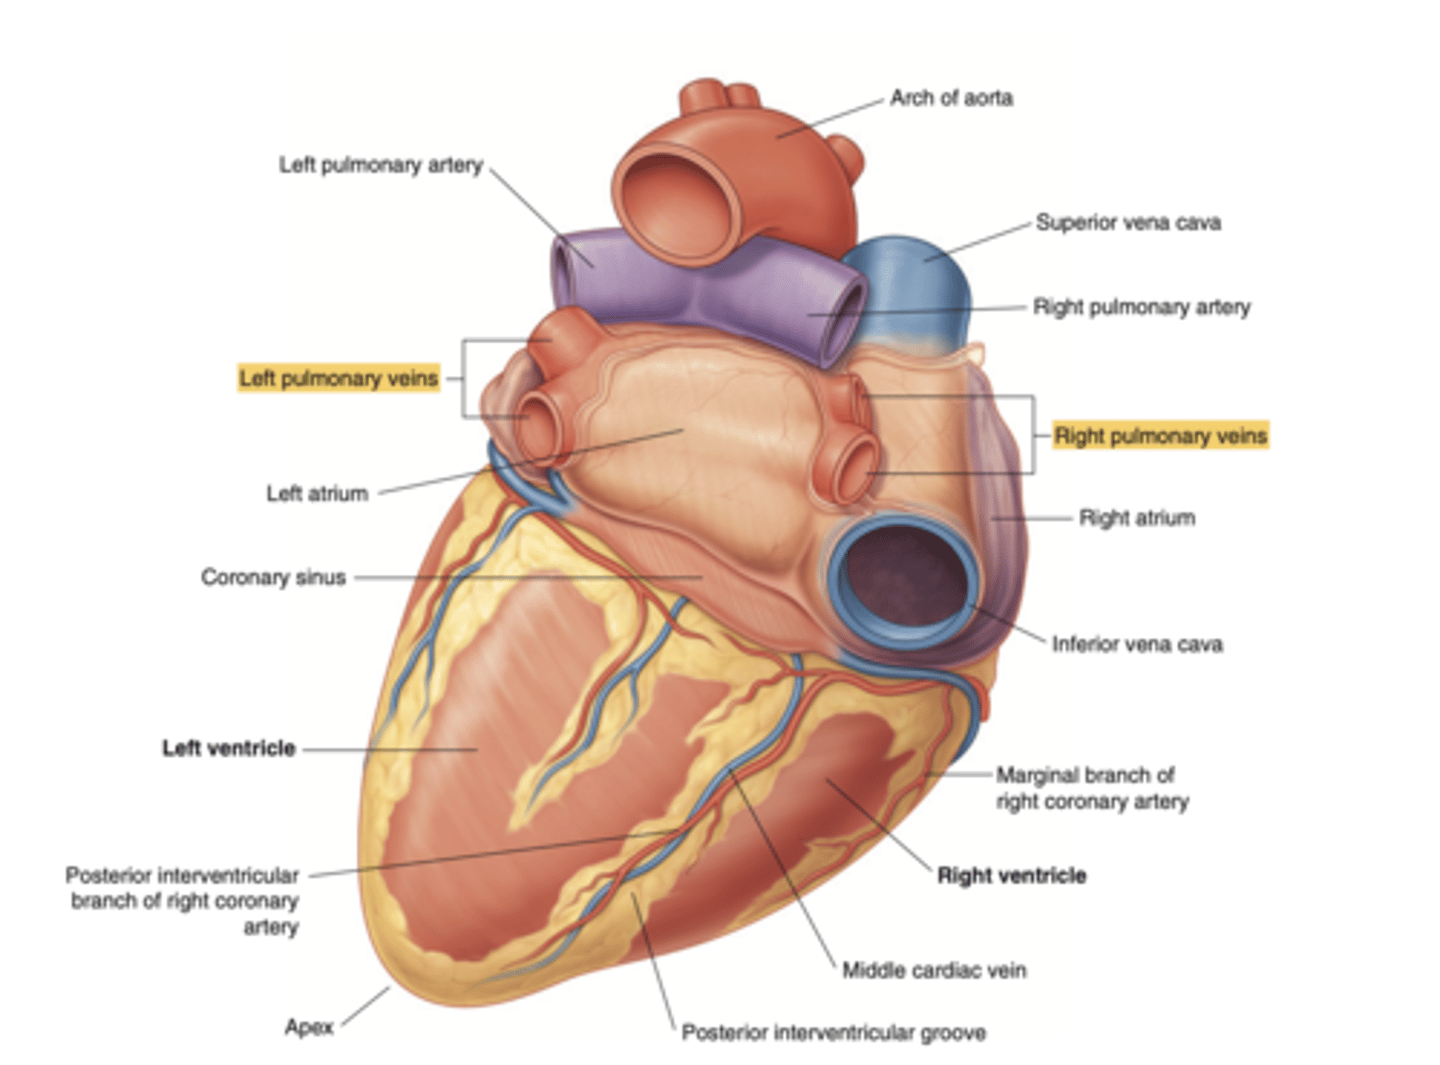

What structures enter the right atrium posteriorly?

. Coronary sinus (visible only in the posterior view)

Show the position of the coronary sinus in the posterior view of the heart and its function

collects deoxygenated blood from most of the heart's venous system

delivers it to the right atrium for reoxygenation.

Show the position of the ventricles and auricles in the posterior view

Which veins enter the left atrium?

left pulmonary veins

right pulmonary veins

ALLOWS OXIGENATED BLOOD FROM THE LUNGS TO ENTER THE HEART